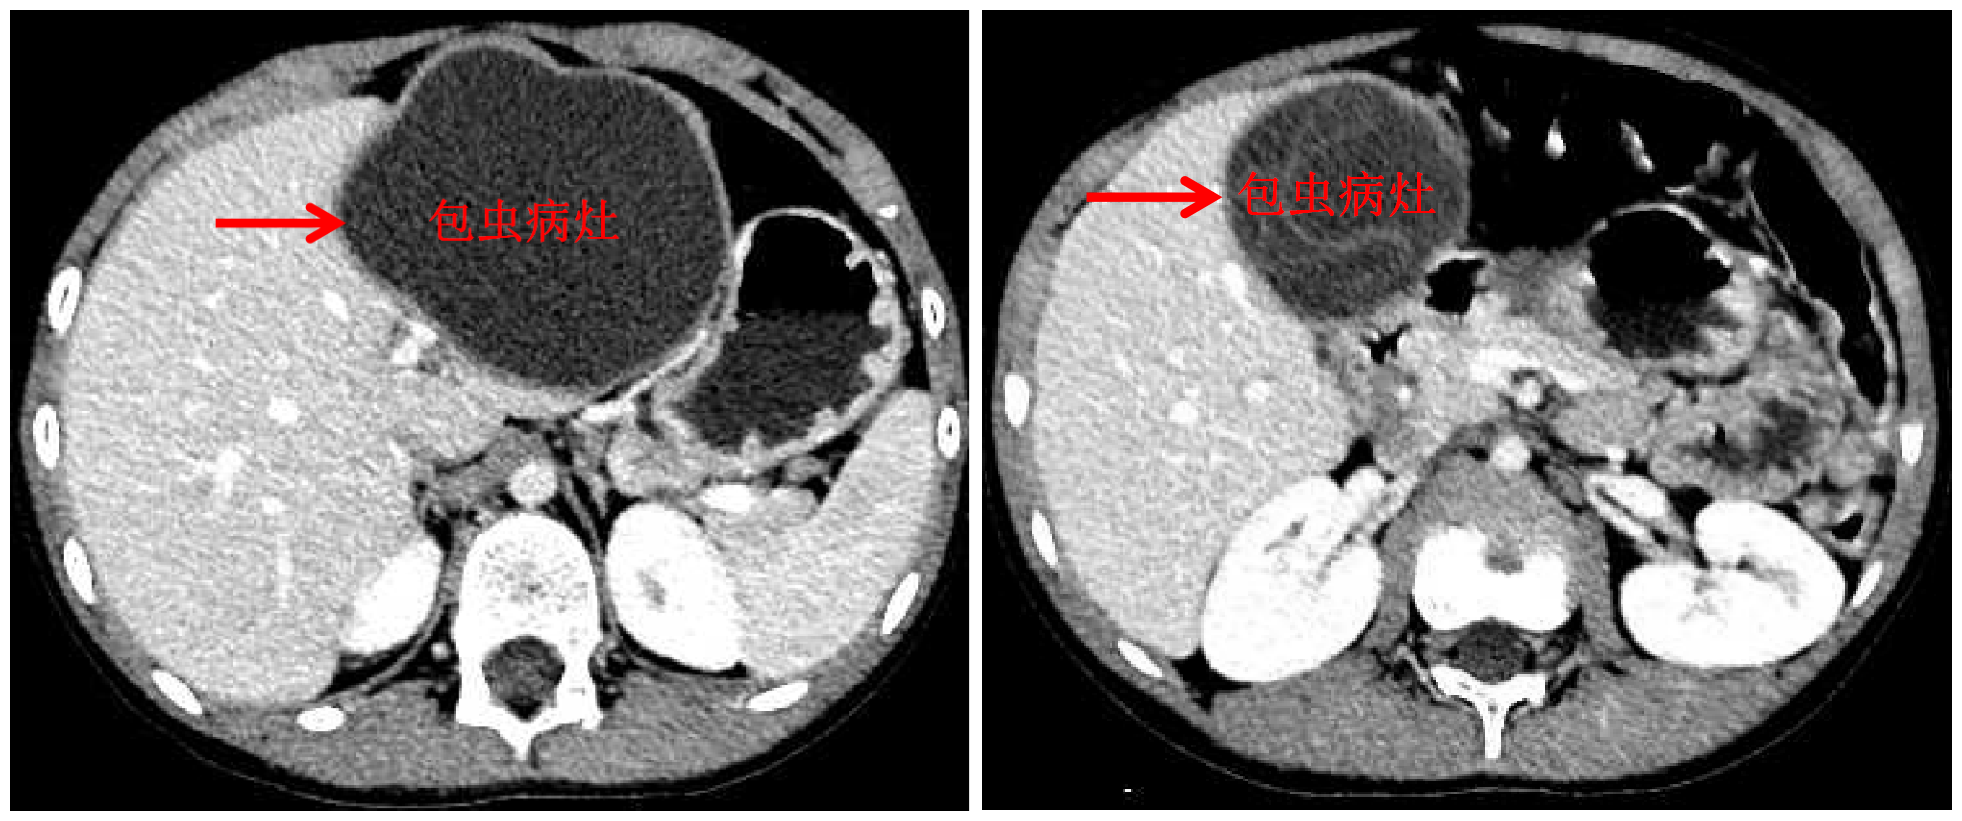

首页网10月13日电 国庆前,8岁的小扎西被父亲带到了西藏大学附属拉萨市人民医院普外科,此次距离孩子确诊肝包虫病已有一年之久。腹部影像显示,小扎西体内的囊型肝包虫病已经侵袭了左肝大部。

面对肝包虫病患儿,心博在线登录入口附属北京清华长庚医院肝胆胰外科援藏医生、现任拉萨市人民医院普外科主任王学栋已经历过丰富的历练——由董家鸿院士带领的清华长庚肝胆胰团队常年深入青海、四川等游牧地区义诊,为终末期肝包虫病患者提供治疗。但对于小扎西,无疑开腹摘除术是更加简单、安全的方法,而腹腔镜下切除病灶,能达成藏族同胞对微创的要求,却是困难重重——病灶巨大,腔镜下解剖及显露肝门困难,且病灶紧贴肝中静脉,保留肝中静脉较困难。

包虫病灶